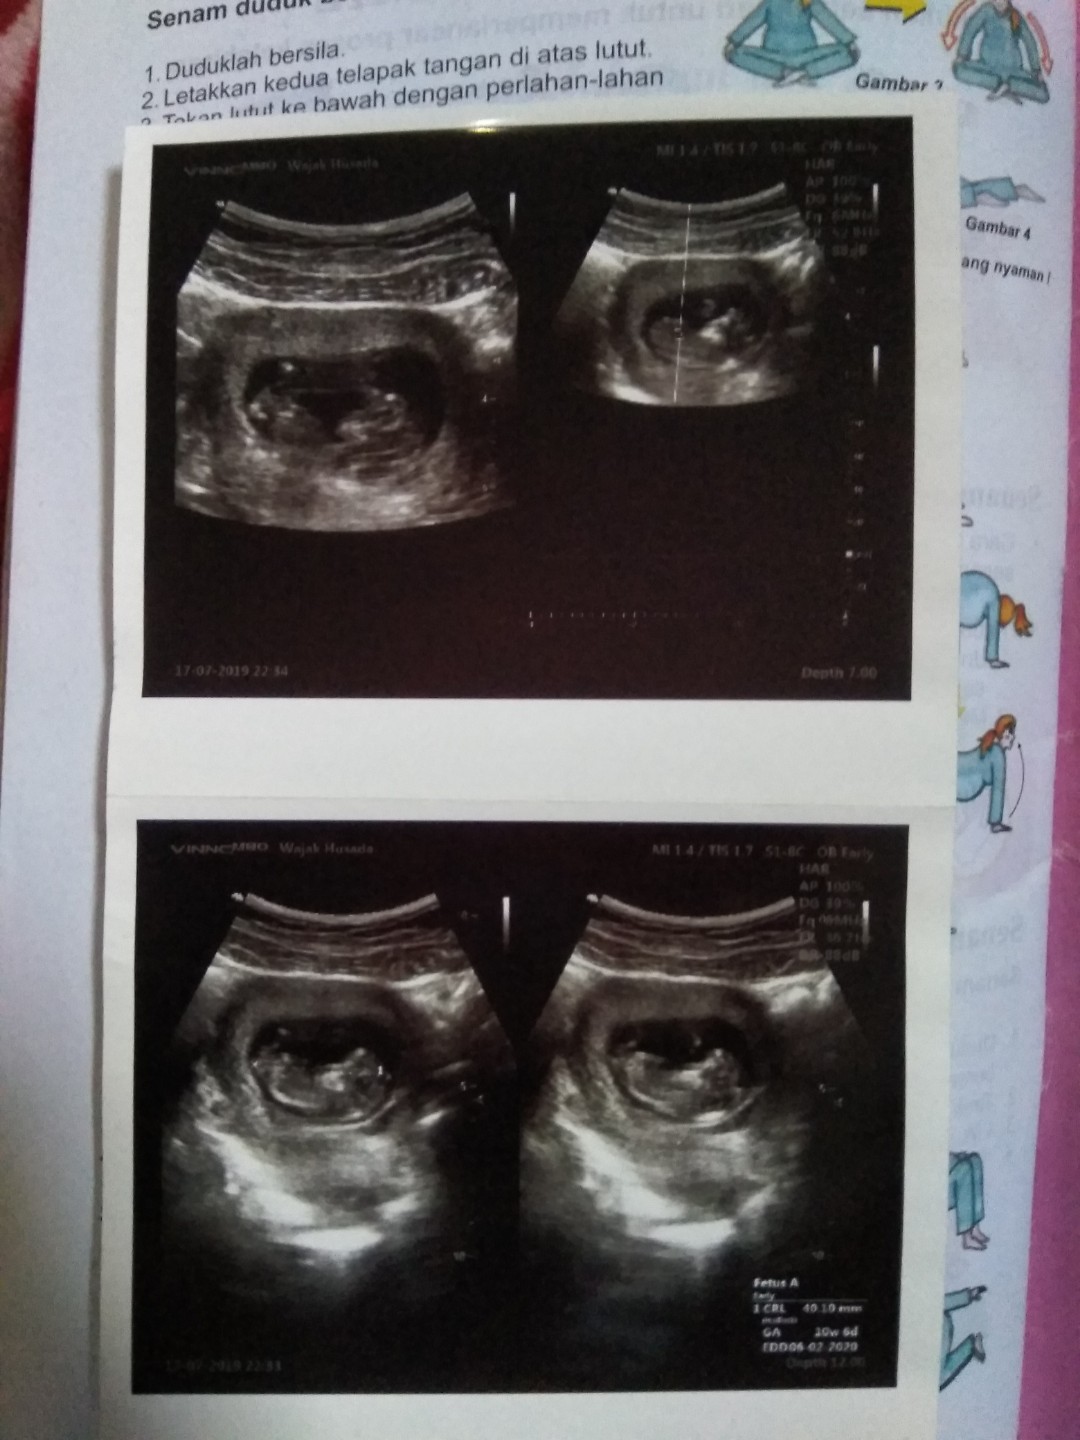

usg

10W 6D

Ini